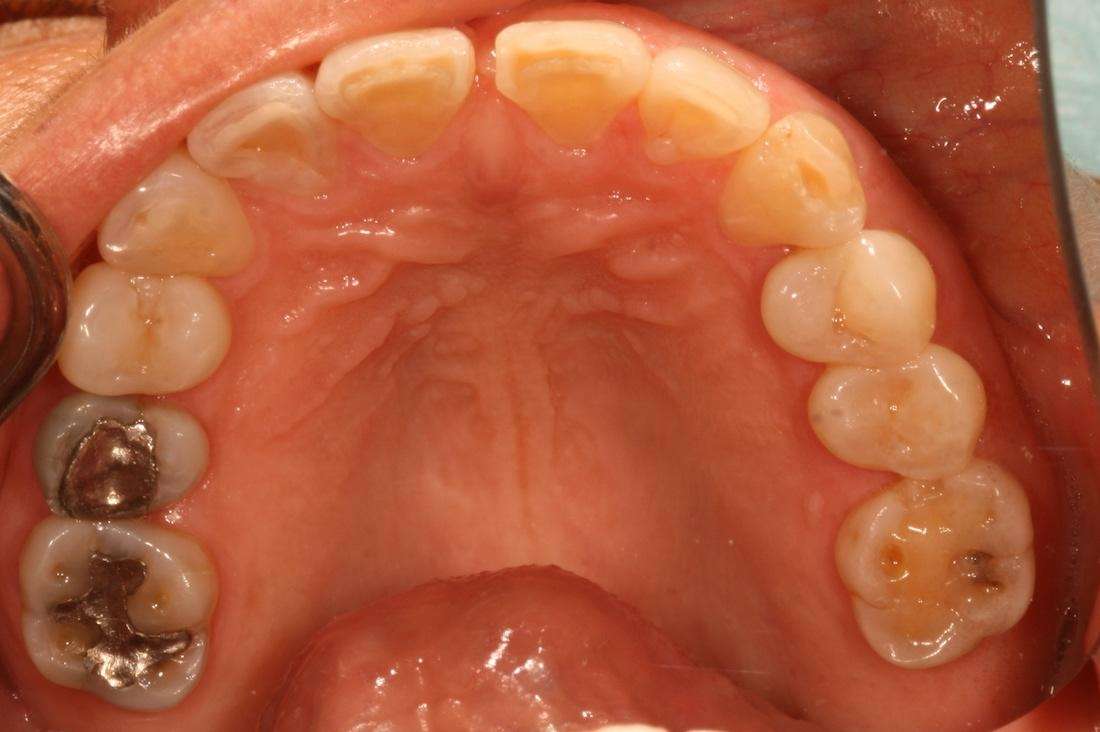

A full smile make-over has been life changing for RP. She only wishes she had done it sooner!

Before

After